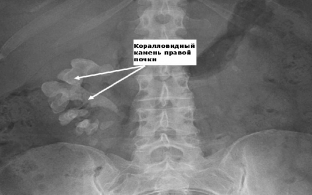

Важливу інформацію при сечокам'яній хворобі надає рентгенологічне дослідження, яке слід починати з оглядової урографії. На рентгенологічному знімку візуалізуються тіні каменів, що утворилися, що дозволяє уточнити місце їх локалізації. Після введення контрастної речовини проводять екскреторну урографію, яка дозволяє отримати інформацію про анатомічні та функціональні зміни в нирках. Визначають ступінь розширення ниркових структур, характерні зміни. Часто рентгенконтрастна речовина заповнює чашково-лоханкову систему нирок до рівня їх обструкції. У пацієнтів з повністю порушеною прохідністю виконують ретроградну уретеропієлографію.